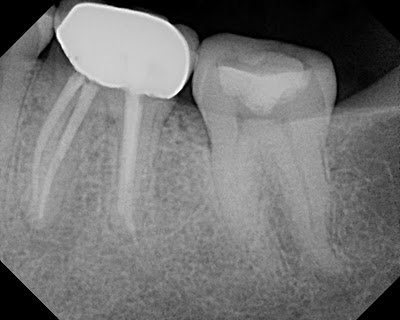

This patient came to our office today for consultation. Pt reports that RCT was done many years ago without any issues. Last year he traveled to Mexico for some dental work. The crowns were placed on #30 & #31. A periapical lesion has now developed on the mesial root of #30. My diagnosis is: prior RCT w/ symptomatic apical periodontitis. Coronal leakage is identified radiographically on mesial and distal margin. In this case, you could easily say the root canal failed. However, the inadaquate coronal seal on #30, in my opinion, is just as likely the cause for the periapical lesion on the MB root.

In our practice at Superstition Spring Endodontics, we would diagnose #30 as: Prior RCT with SAP (symptomatic apical periodontitis – percussion pain) with coronal leakage. Retreatment would be recommended. We would explain to the patient that for long term success, we need to prevent any leakage from above. (We would also recommend evaluation of mesial margin #31 by general dentist)